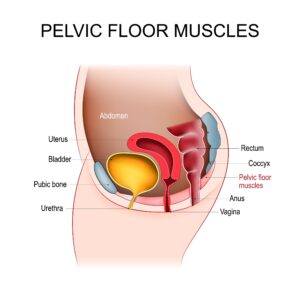

What is Pelvic Floor?

Pelvic floor is not just muscles in pelvic floor.

Pelvic floor is not just muscles in pelvic floor.

The pelvic floor is a group of muscles, ligaments, and tissues that support the pelvic organs, including the bladder, uterus, and rectum. During pregnancy and childbirth, these structures undergo significant stress and stretching. It’s essential to recognize that postpartum recovery involves restoring strength and function to this area.